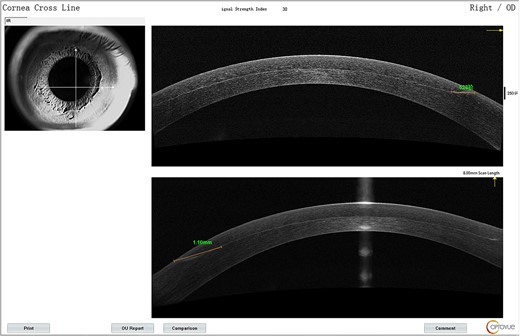

The lower part of the flap appeared grayish-white from Day 1.On AS-OCT, the lesion extent was 1.1 mm from the edge (Fig. 1) with reflectivity becoming higher. It was deemed as corneal edema and postoperative immunological response. The patient was prescribed fluorometholone 0.1% eye drops and 0.3% Ofloxacin eye drops for both eyes and asked to return in 5 days for reevaluation.